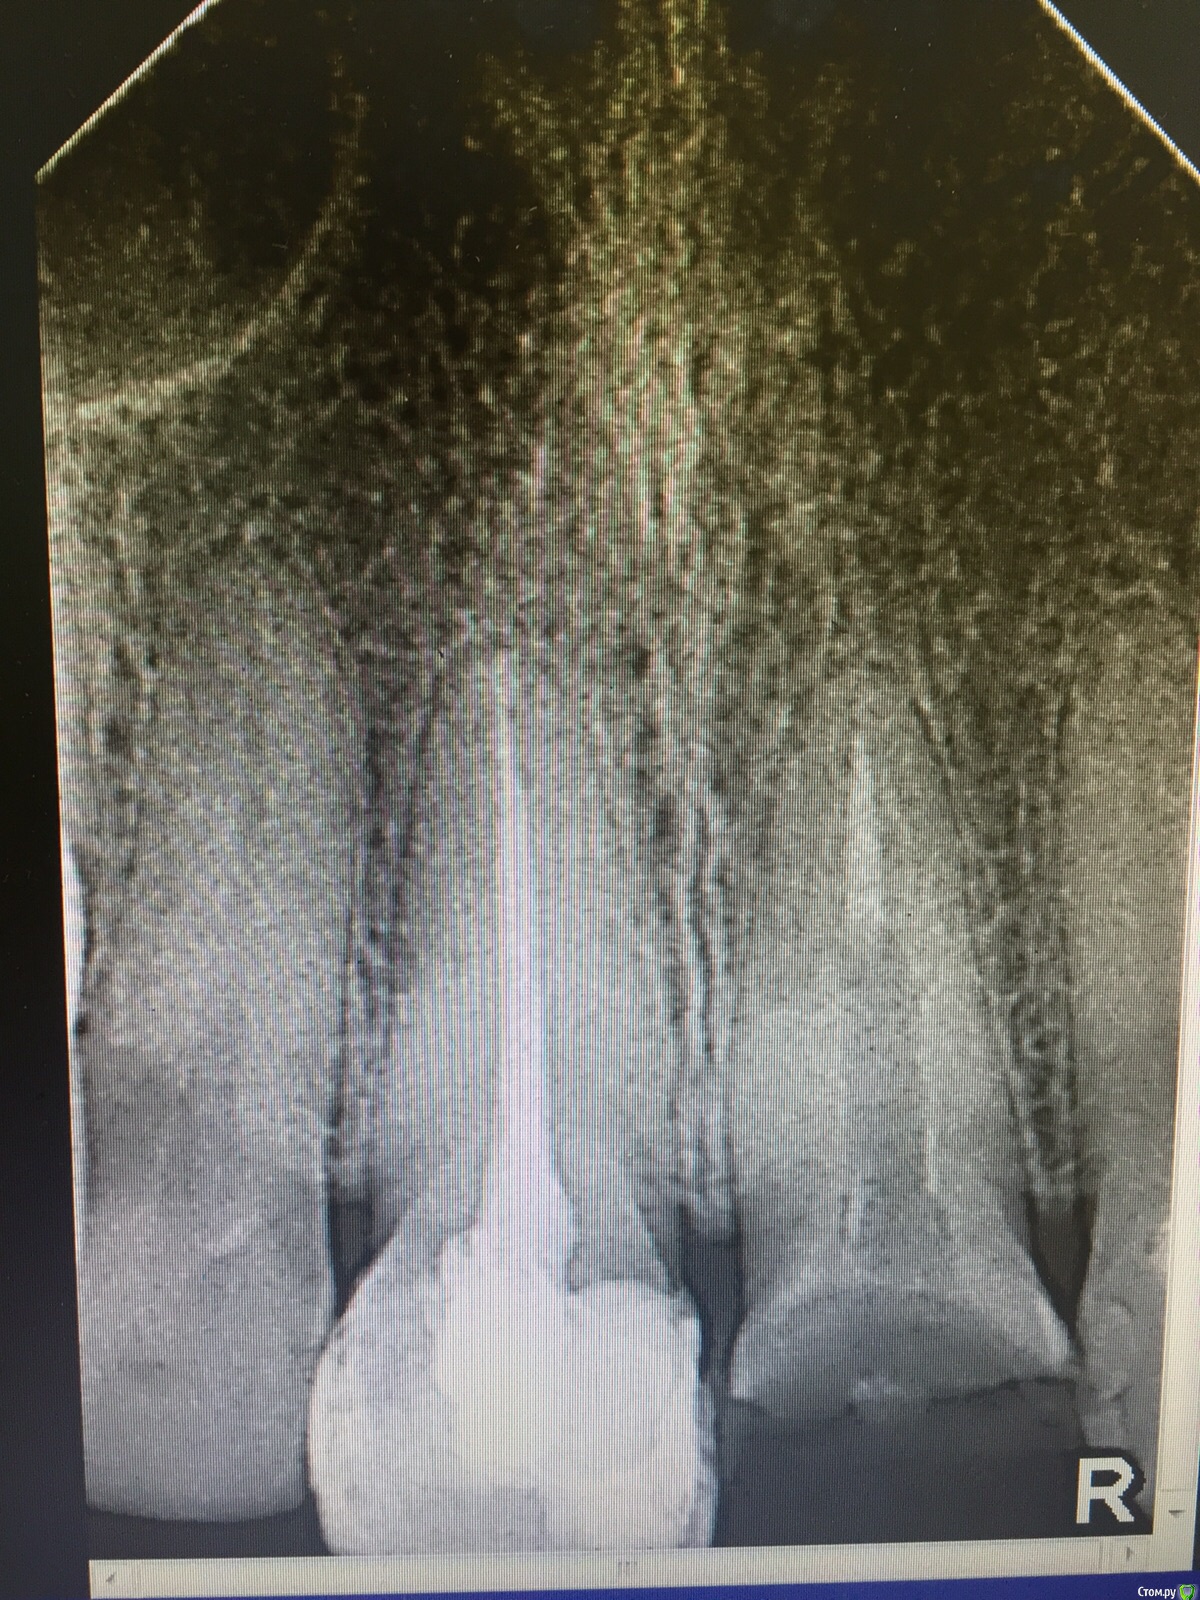

Нюша Опубликовано 15 декабря, 2015 Поделиться Опубликовано 15 декабря, 2015 Доброго времени суток. Очень нужно профессиональное мнение.Перед протезированием 2 верхних центральных зубов, доктор сказал, что надо перелечить каналы несмотря на то, что они запломбированы качественно и никогда не возникало проблем с момента их первоначальной пломбировки. Во время работы возникла боль как на живом зубе на что доктор сказал, что это реакция тканей вне канала. После посещения остаётся боль при надавливании и постукивании уже 2 дня. Стоит ли ставить коронки или есть недостатки в перепломбировке или что то мне повредили в канале? Беспокоит то, что зуб депульпировали и пролечили канал 10 лет назад, и он никогда не беспокоил. А тут после перепломбировки стал болеть. Прилагаю снимки обоих зубов где перепломбировывали каналы. На одном планируют поставить культевую вкладку. Болит тот, где не нужна культевая вкладка (более целый).Пожалуйста, посоветуйте, в чем проблема? Спасибо заранее. Ссылка на комментарий

kozloff Опубликовано 16 декабря, 2015 Поделиться Опубликовано 16 декабря, 2015 Боль может сохраняться до 7 -14 дней. Это нормально. Канал запломбирован хорошо. Ссылка на комментарий

St. Опубликовано 16 декабря, 2015 Поделиться Опубликовано 16 декабря, 2015 Не переживайте, так бывает, ничего страшного. По снимку всё хорошо. Ссылка на комментарий